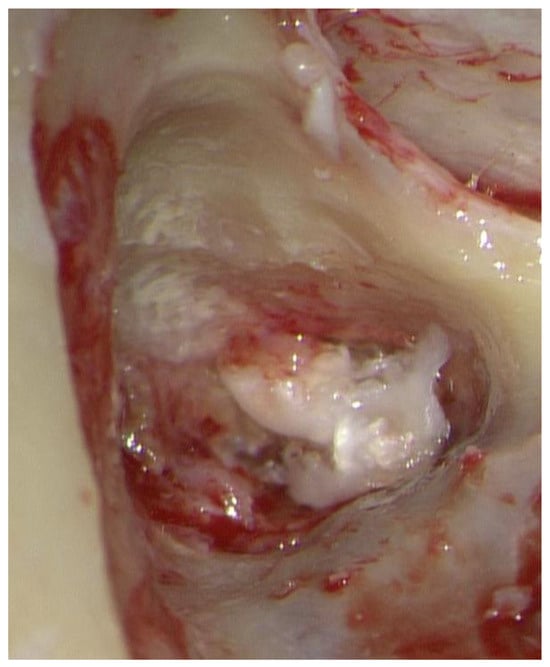

2. Case Report